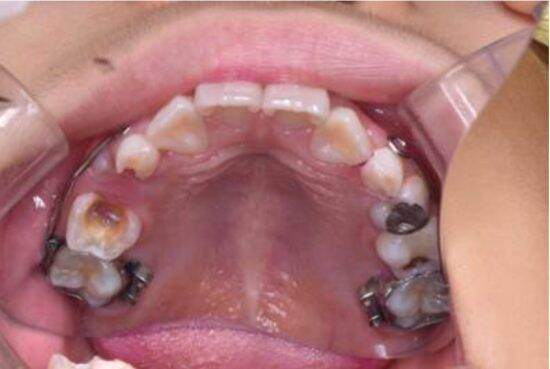

・初期のむし歯や歯周病の早期発見、進行予防改善対策が練れる

子どもや高齢者、全身疾患を持つ方は特に注意